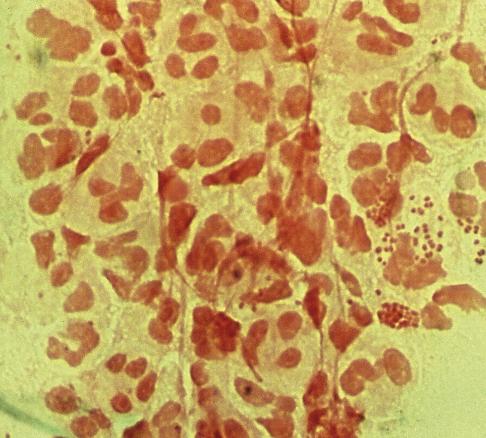

Le diagnostic est évoqué sur l’anamnèse et la clinique. Il est confirmé par l’analyse polymerase chain-reaction (PCR) d’un écouvillonnage rectal détectant simultanément Neisseria gonorrhoeae (fig. 2 ) et Chlamydia trachomatis. Ce prélèvement permet également la réalisation d’un antibiogramme.

Le diagnostic est évoqué sur l’anamnèse et la clinique. Il est confirmé par l’analyse polymerase chain-reaction (PCR) d’un écouvillonnage rectal détectant simultanément Neisseria gonorrhoeae (